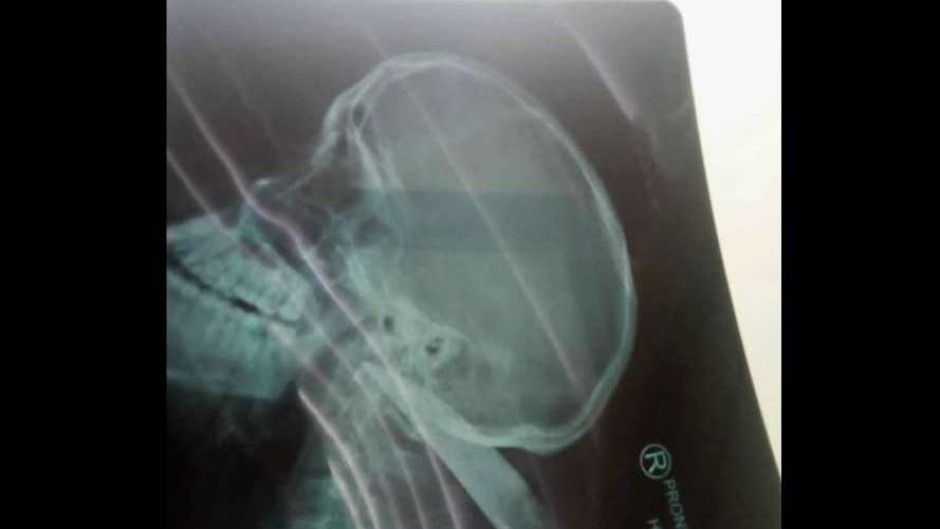

Please note: The following report contains visuals of a graphic nature.

The victim managed to return to the school’s premises, with the knife still lodged in his neck, to seek assistance.